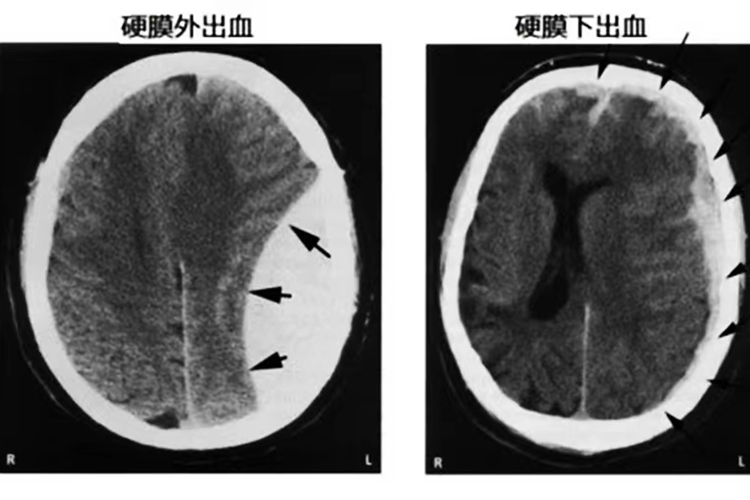

影像学表现:CT可以直接显示硬脑膜外血肿,表现为颅骨内板与硬脑膜之间的双凸镜形或弓形高密度影。而硬脑膜下血肿CT扫描可以确诊急性或亚急性硬脑膜下血肿,表现为脑表面新月形高密度、混杂密度或等密度影,多伴有脑挫裂伤和脑受压。